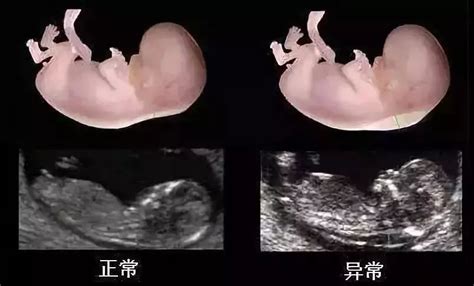

死胎或早产、畸形的概率增加。母体长期血糖增高,可伴发小血管的病变,影响胎盘血液供应,引起胚胎发育异常,胎儿畸形发生率高达25%到42%,胎儿生长受限发生率为21%,容易发生流产或早产,甚至死亡流产率达到15%到30%。